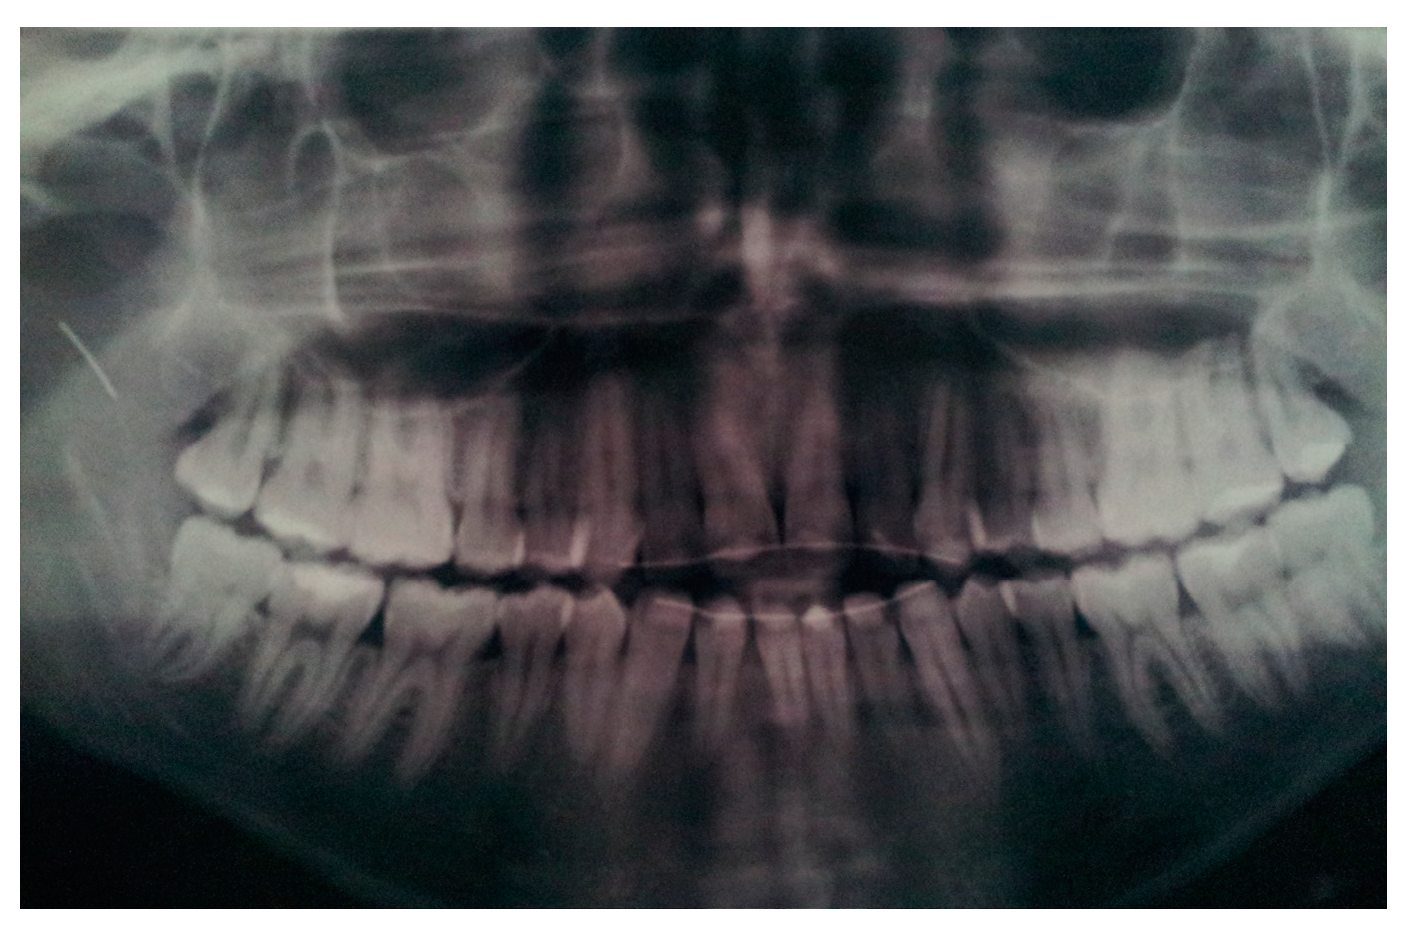

- Shah, A.; Gill, D.S.; Tredwin, C.; Naini, F.B. Diagnosis and Management of Supernumerary Teeth. Dent. Updat. 2008, 35, 510–520. [Google Scholar] [CrossRef]

| Case 2 Impacted teeth in Pfeiffer Syndrome | 0.5 mm | 0.3 mm | 0.6 mm | |

| Case 3 Impacted teeth in Apert Syndrome | 0.3 mm | 0.5 mm | 0.4 mm | 0.5 mm |

| Case 4 Impacted teeth | 0.3 mm | 0.2 mm |